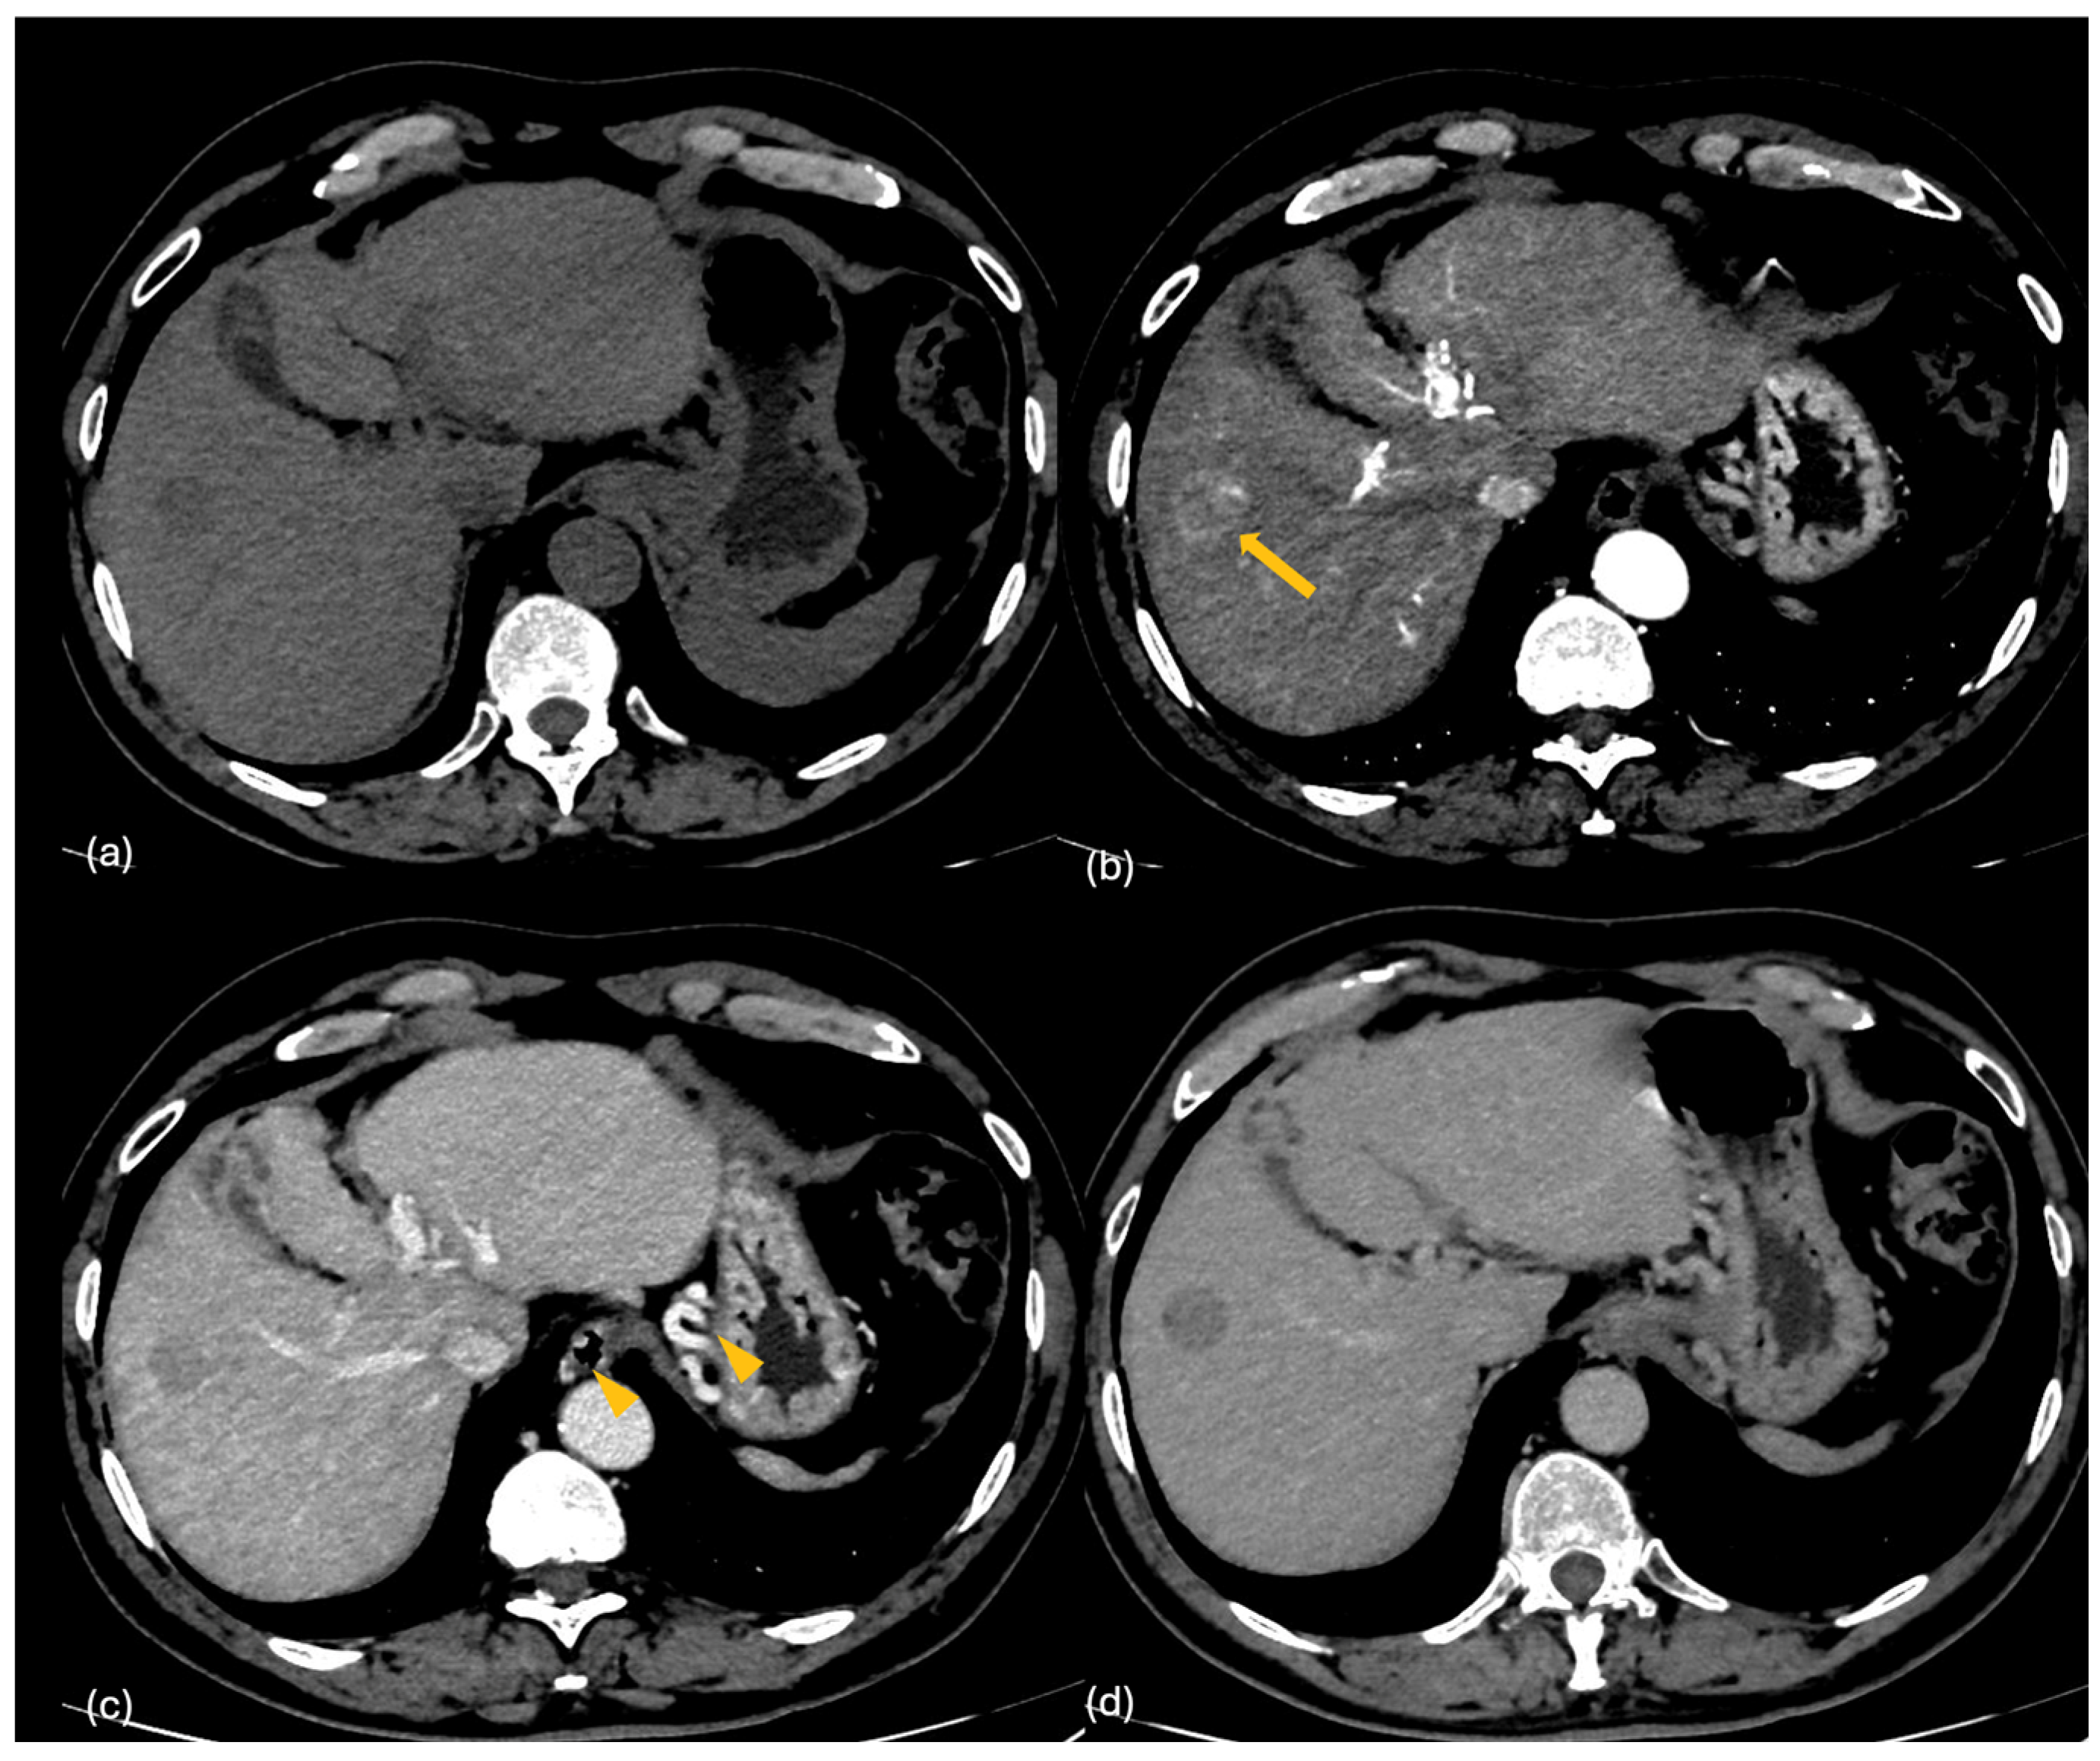

2.2. CT